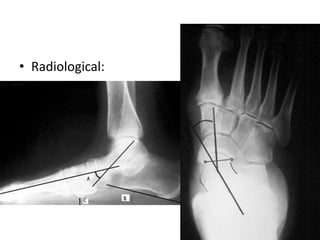

• Radiological:

Stages:

- Described by

Johnson and

Strom, 4 stages